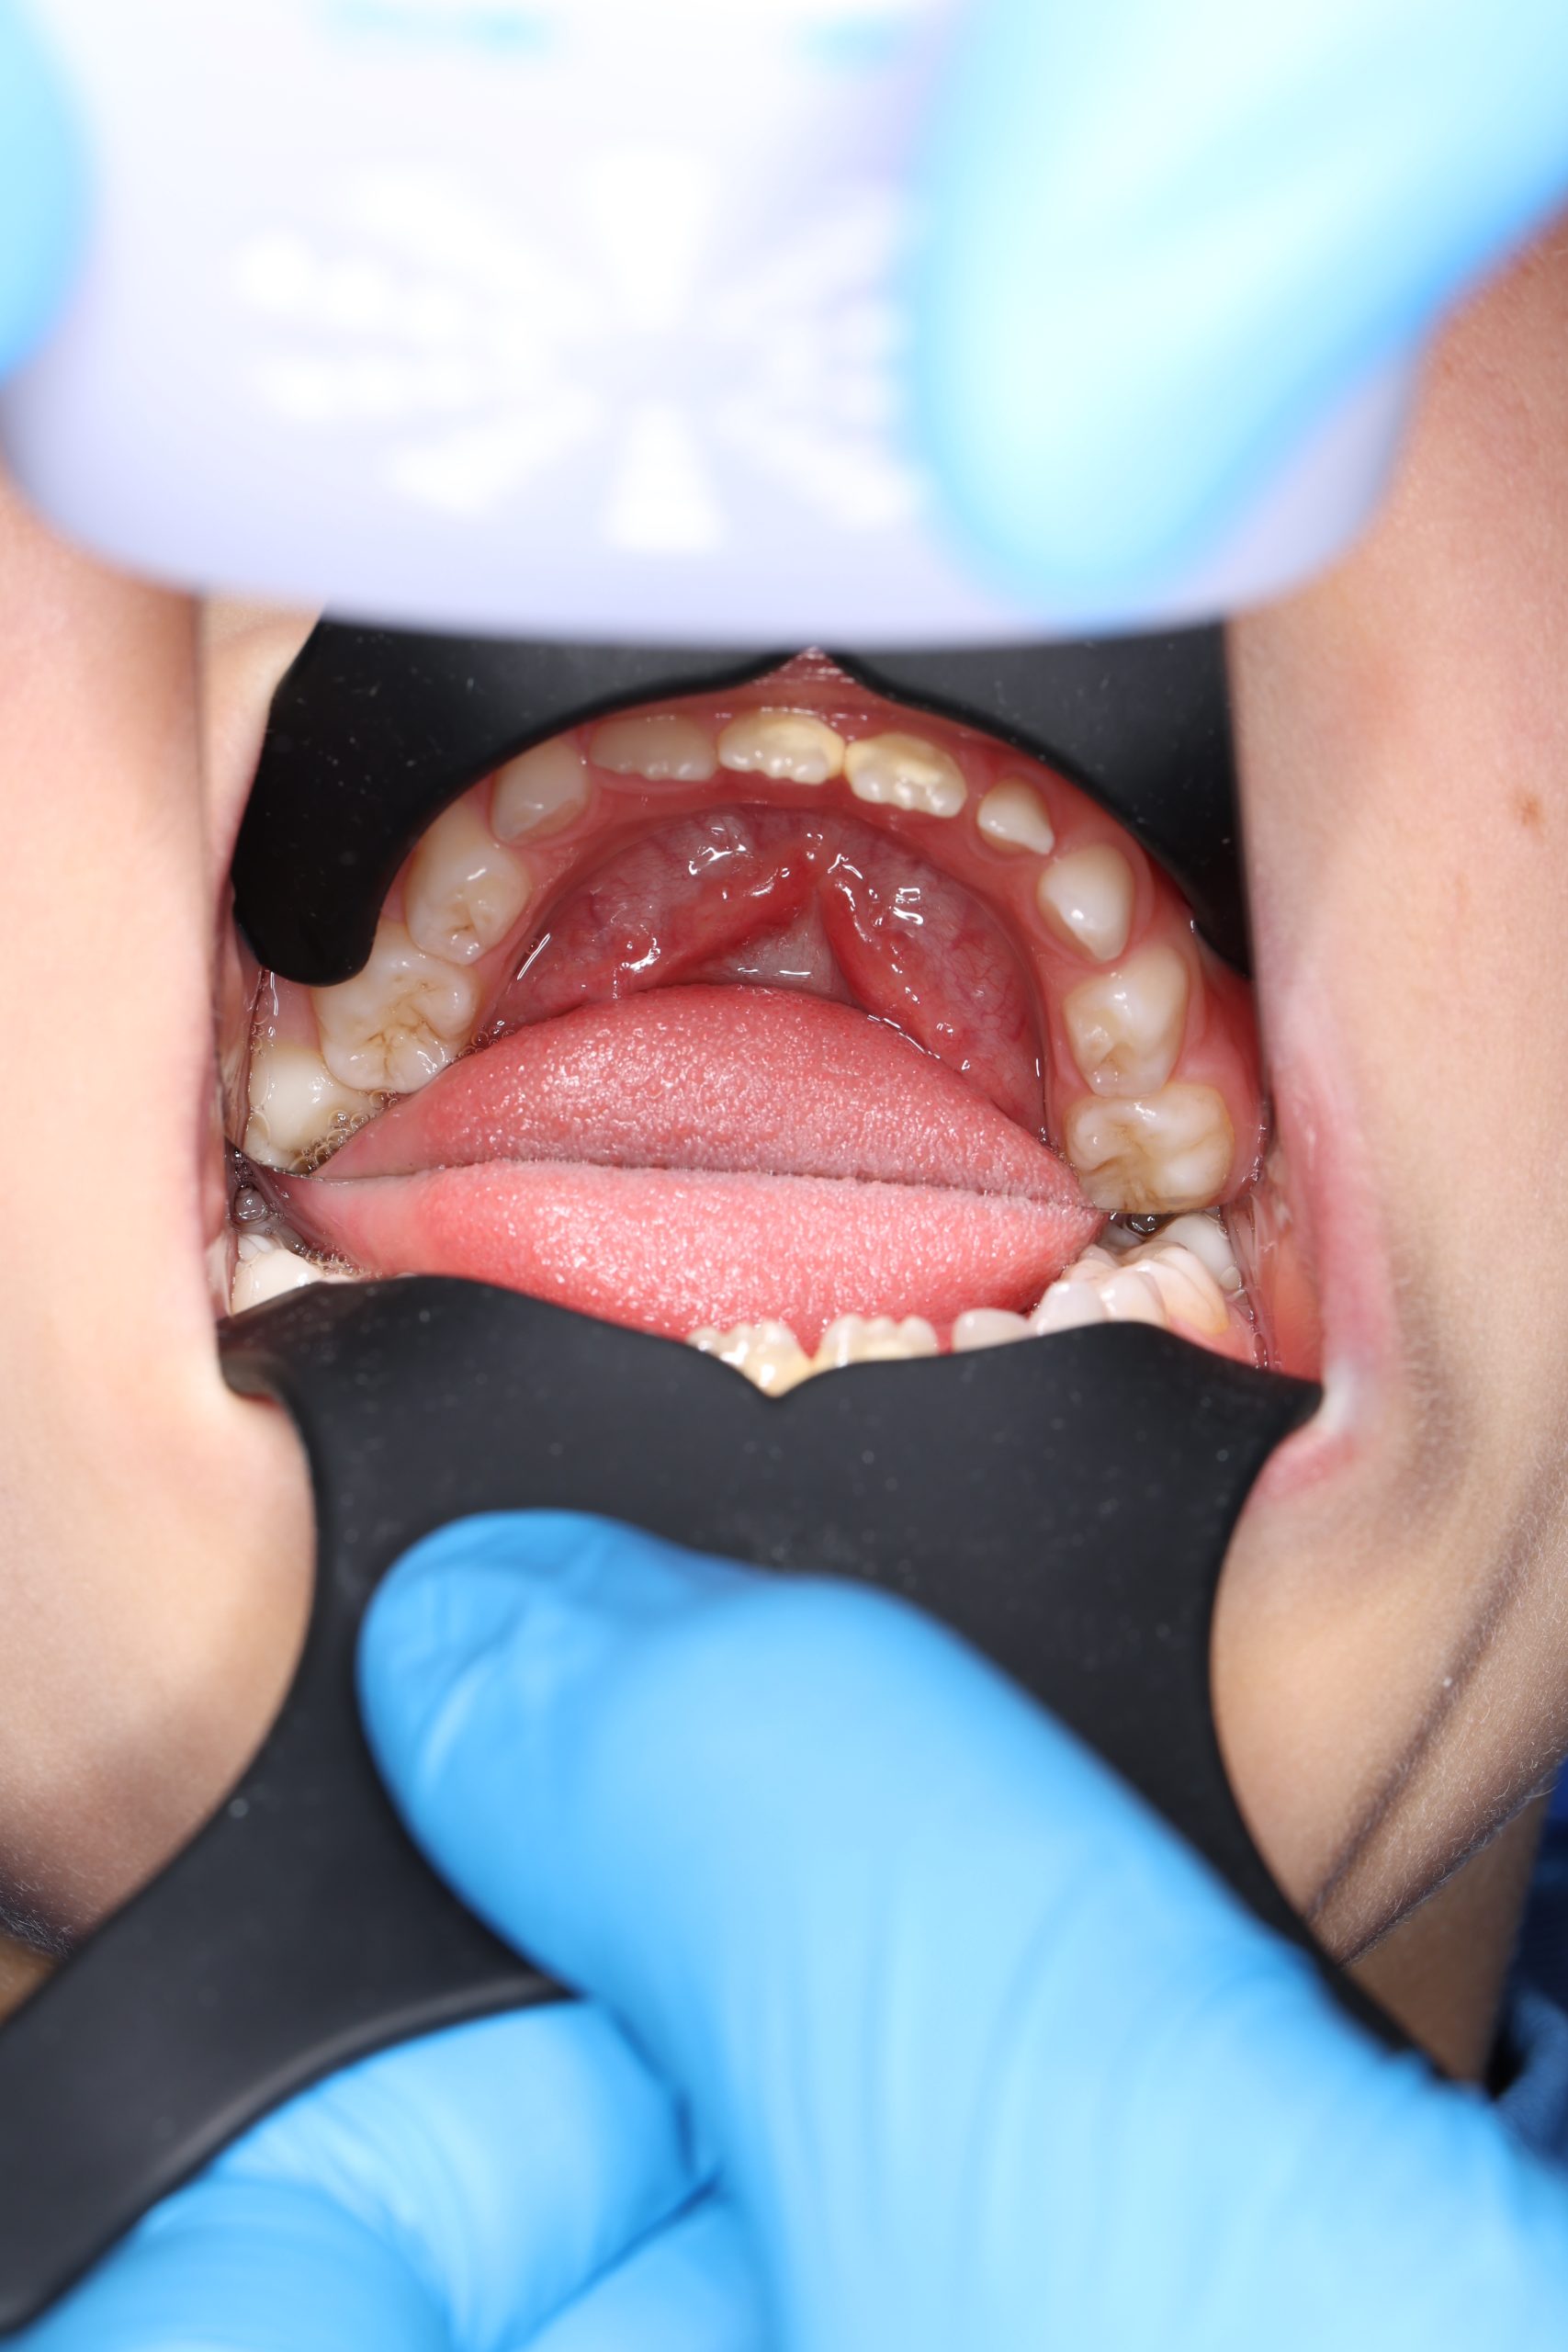

We examine the condition of teeth, gums, and bite. - Plaque Disclosure with Special Indicators

Areas that weren’t cleaned well appear purple. The darker the shade, the older the plaque. This helps both kids and parents understand where brushing needs to improve. - Brushing Training & Home Care Tools Selection

Together with your child, we practice brushing techniques, correct mistakes, and provide personalized recommendations. We advise whether to use manual or electric brushes, floss, interdental brushes, or remineralizing gels. - Plaque Removal with AIRFLOW Prophylaxis Master (EMS, Switzerland)